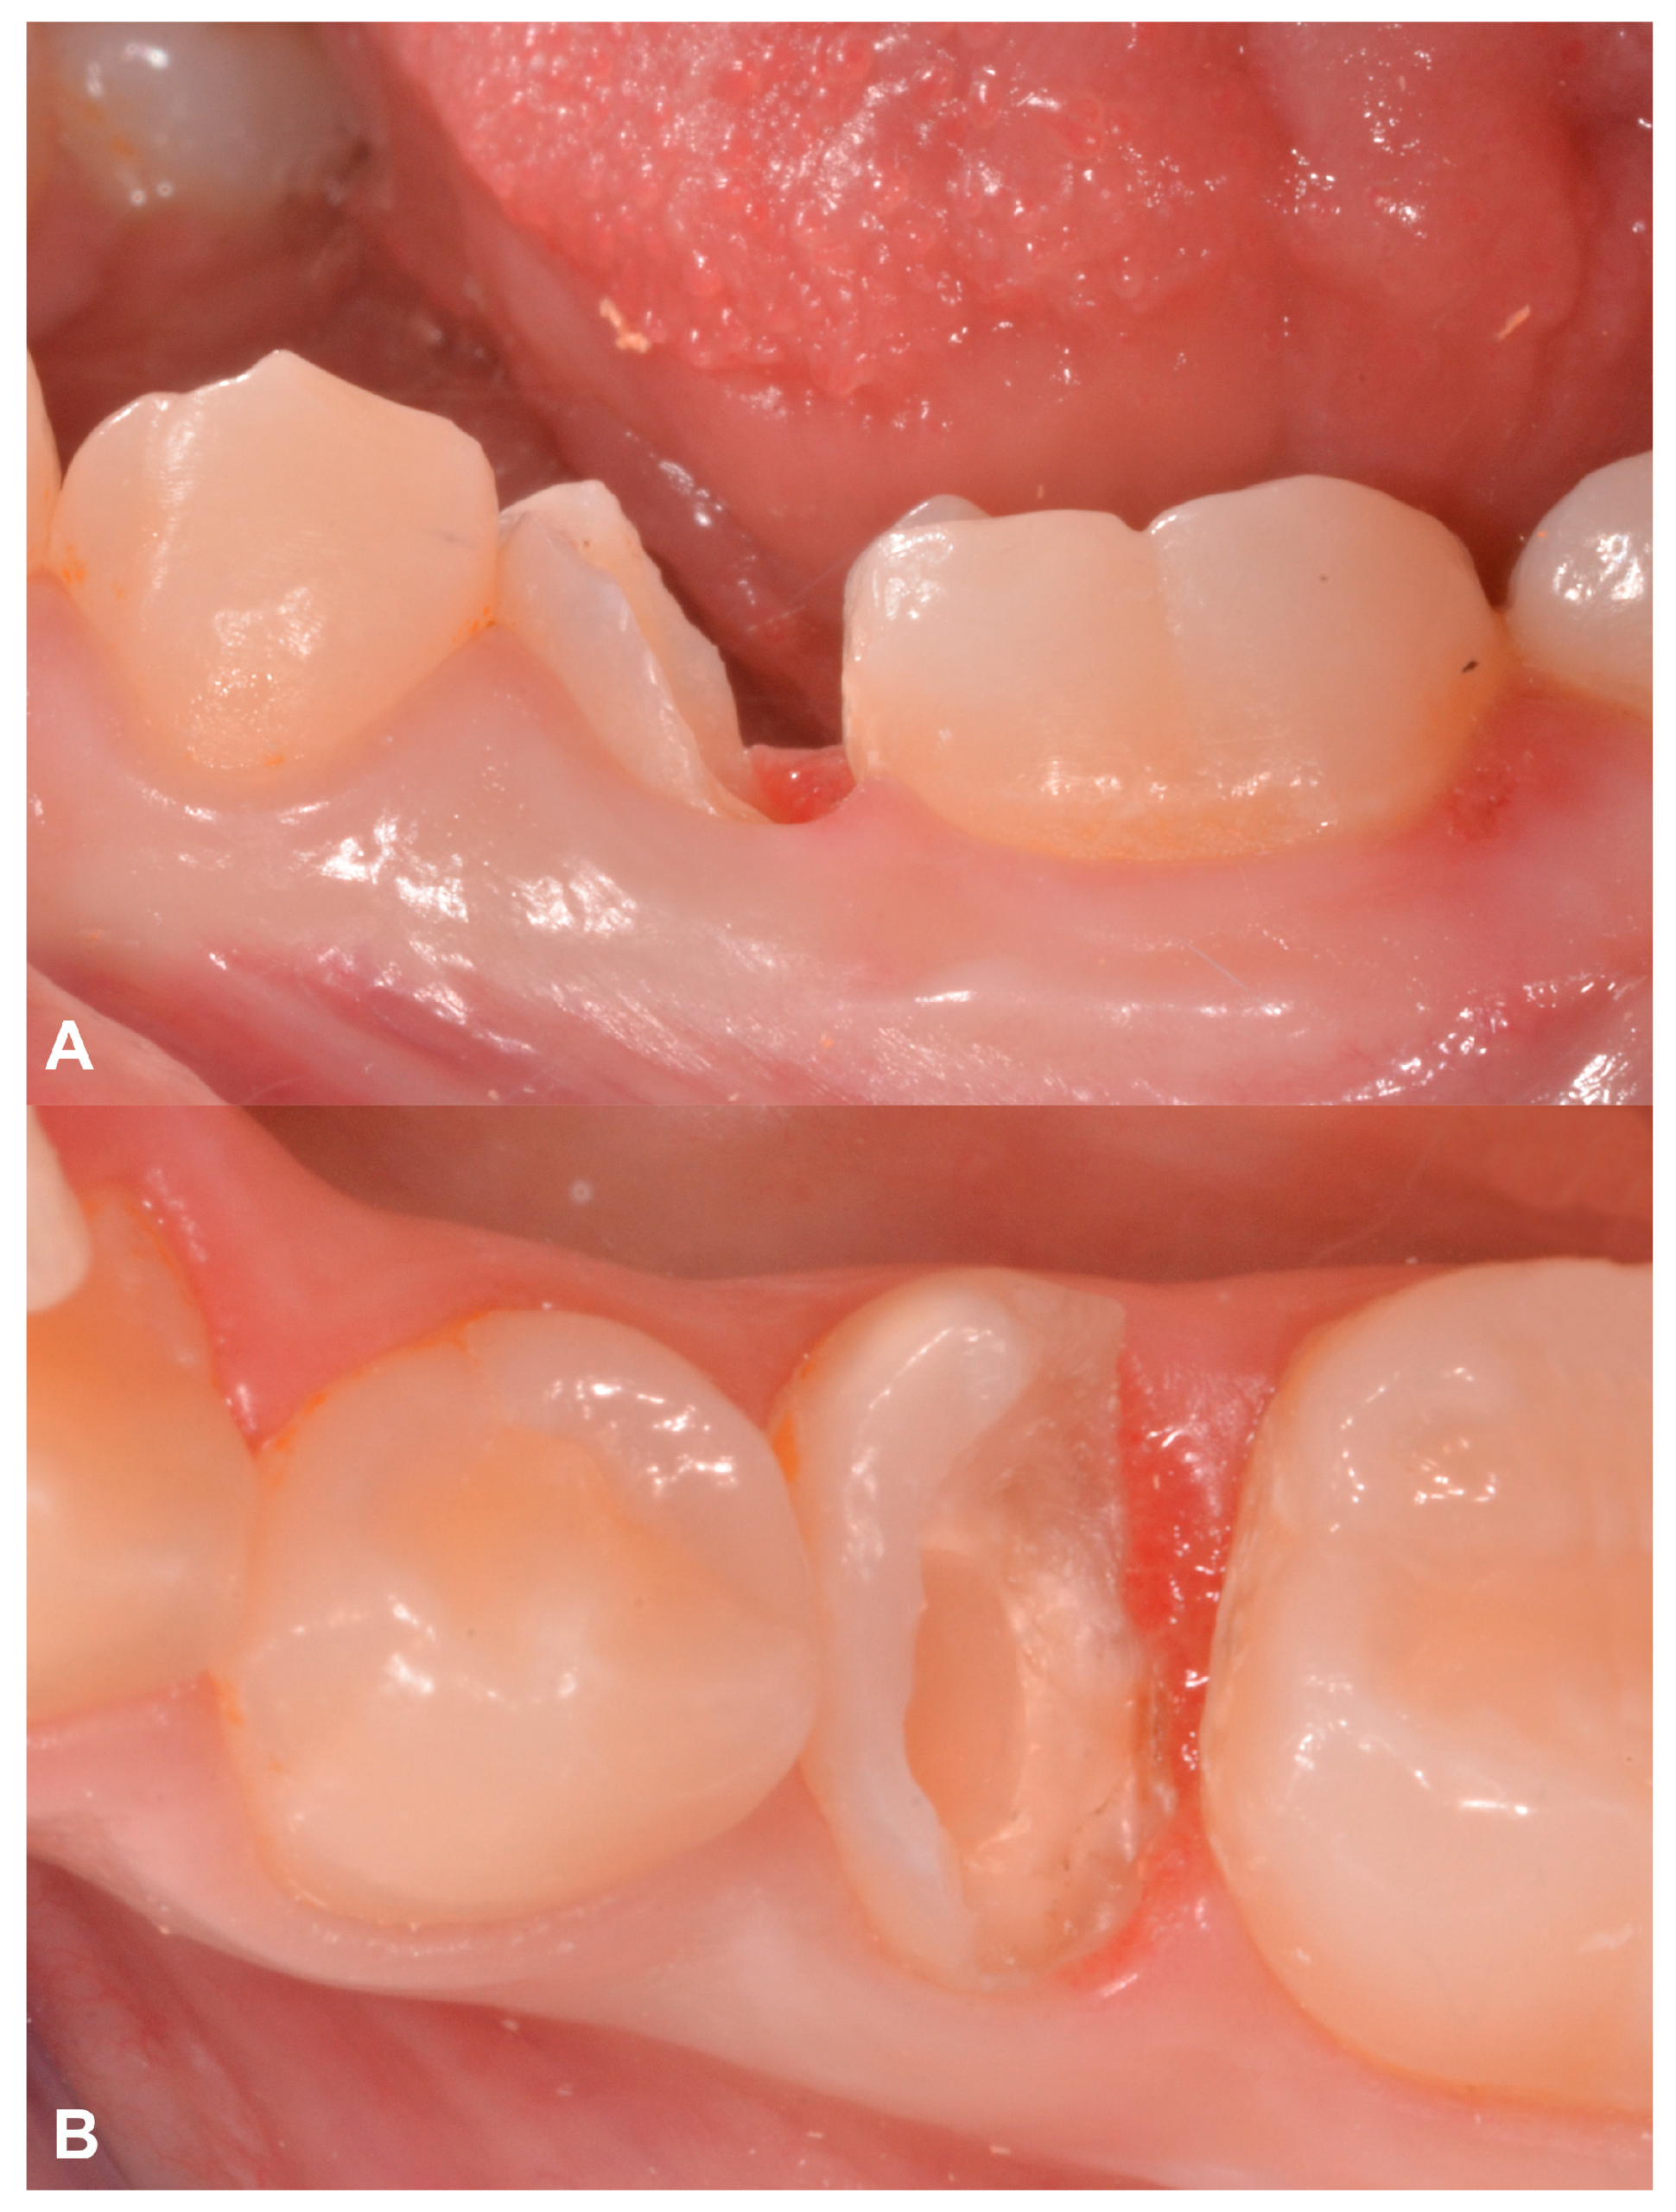

2.4. Case Presentation #3

2.4.1. Anamnesis, Physical Examination

2.4.2. Treatment